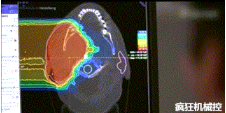

▲360°重離子治療一體機治療腫瘤

360°重離子治療一體可從任何角度用重離子(碳,氦,氧)和質子(氫)照射腫瘤。此外,基于機器人的治療臺可以通過六種方式進行調(diào)整。

光柵掃描被集成到360°重離子治療一體機中,這種極其精確的照射方法以毫米為單位掃描腫瘤,可以保護健康組織且只治療腫瘤區(qū)域。

特別是腫瘤在高度輻射敏感位置或者諸如視神經(jīng)附近的復雜位置,可以通過選擇最佳射束入射角來減小這些器官的損傷。